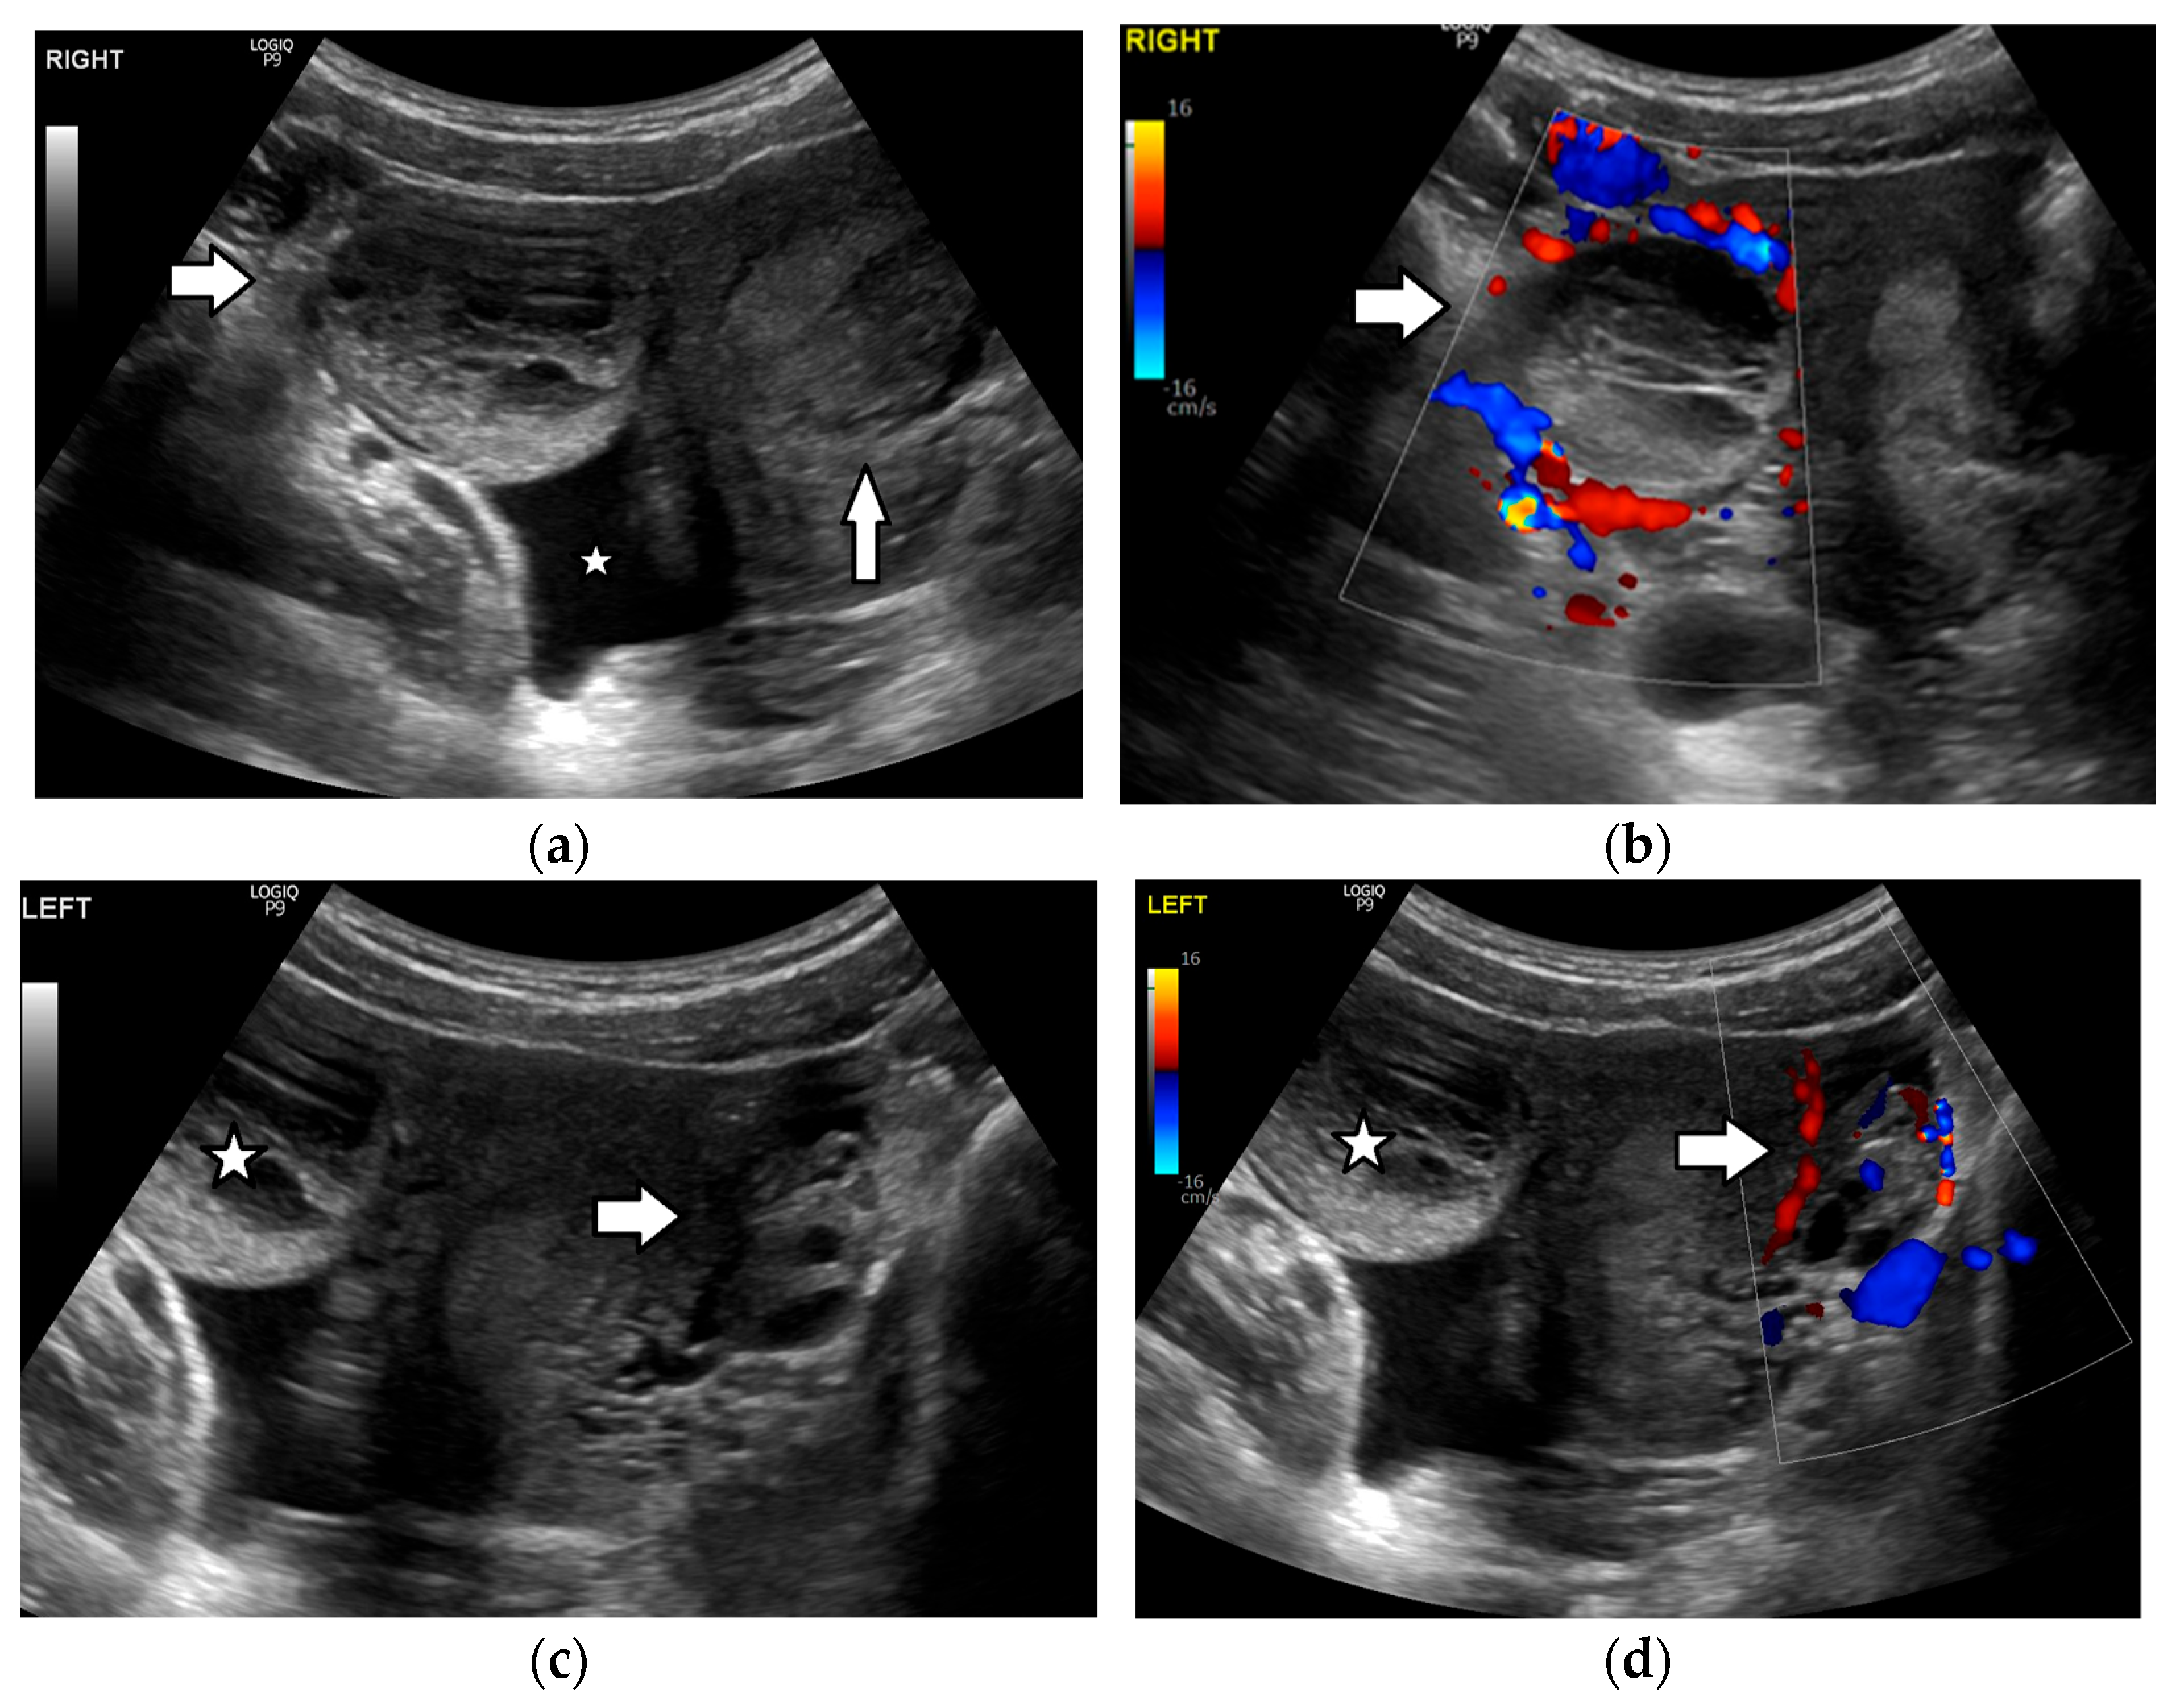

3.3. Ovarian Torsion

3.4. Pelvic Inflammatory Disease/Tubo-Ovarian Abscess